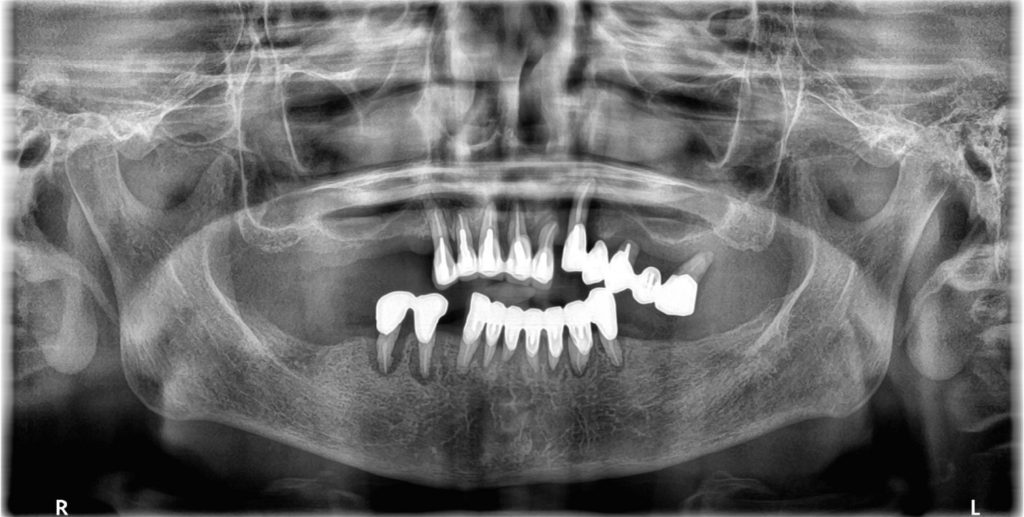

初診時の様子

- パノラマレントゲン写真